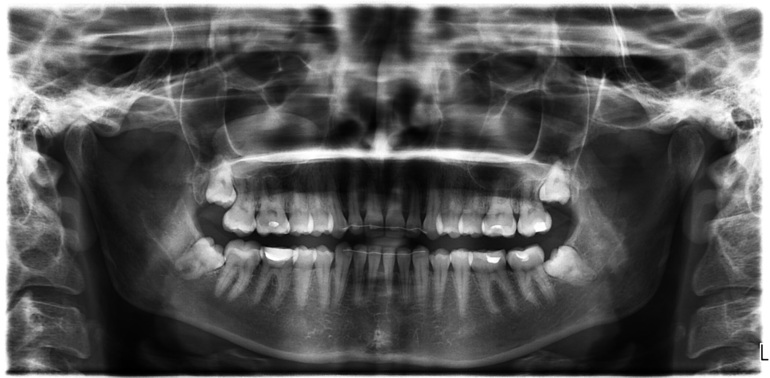

Здравствуйте у меня есть панорамный снимок, хотелось бы узнать какие зубы стоит перелечить, может быть где-то есть кариес под пломбой по снимку? Потому что стоматолог мне без снимка сказал, что все нормально.

Оценить состояние контактных поверхностей на 6-7 зубах верхней и нижней челюсти справа. Возможно, наличие кариеса.

Панорамный рентгеновский снимок дает дополнительную информацию к тому, что врач видит во рту.

На данный момент, я рассказываю Вам ситуацию по панорамному снимку, что не является 100% заключением, кроме того, что 8ые зубы подлежат удалению. Вот это точно.